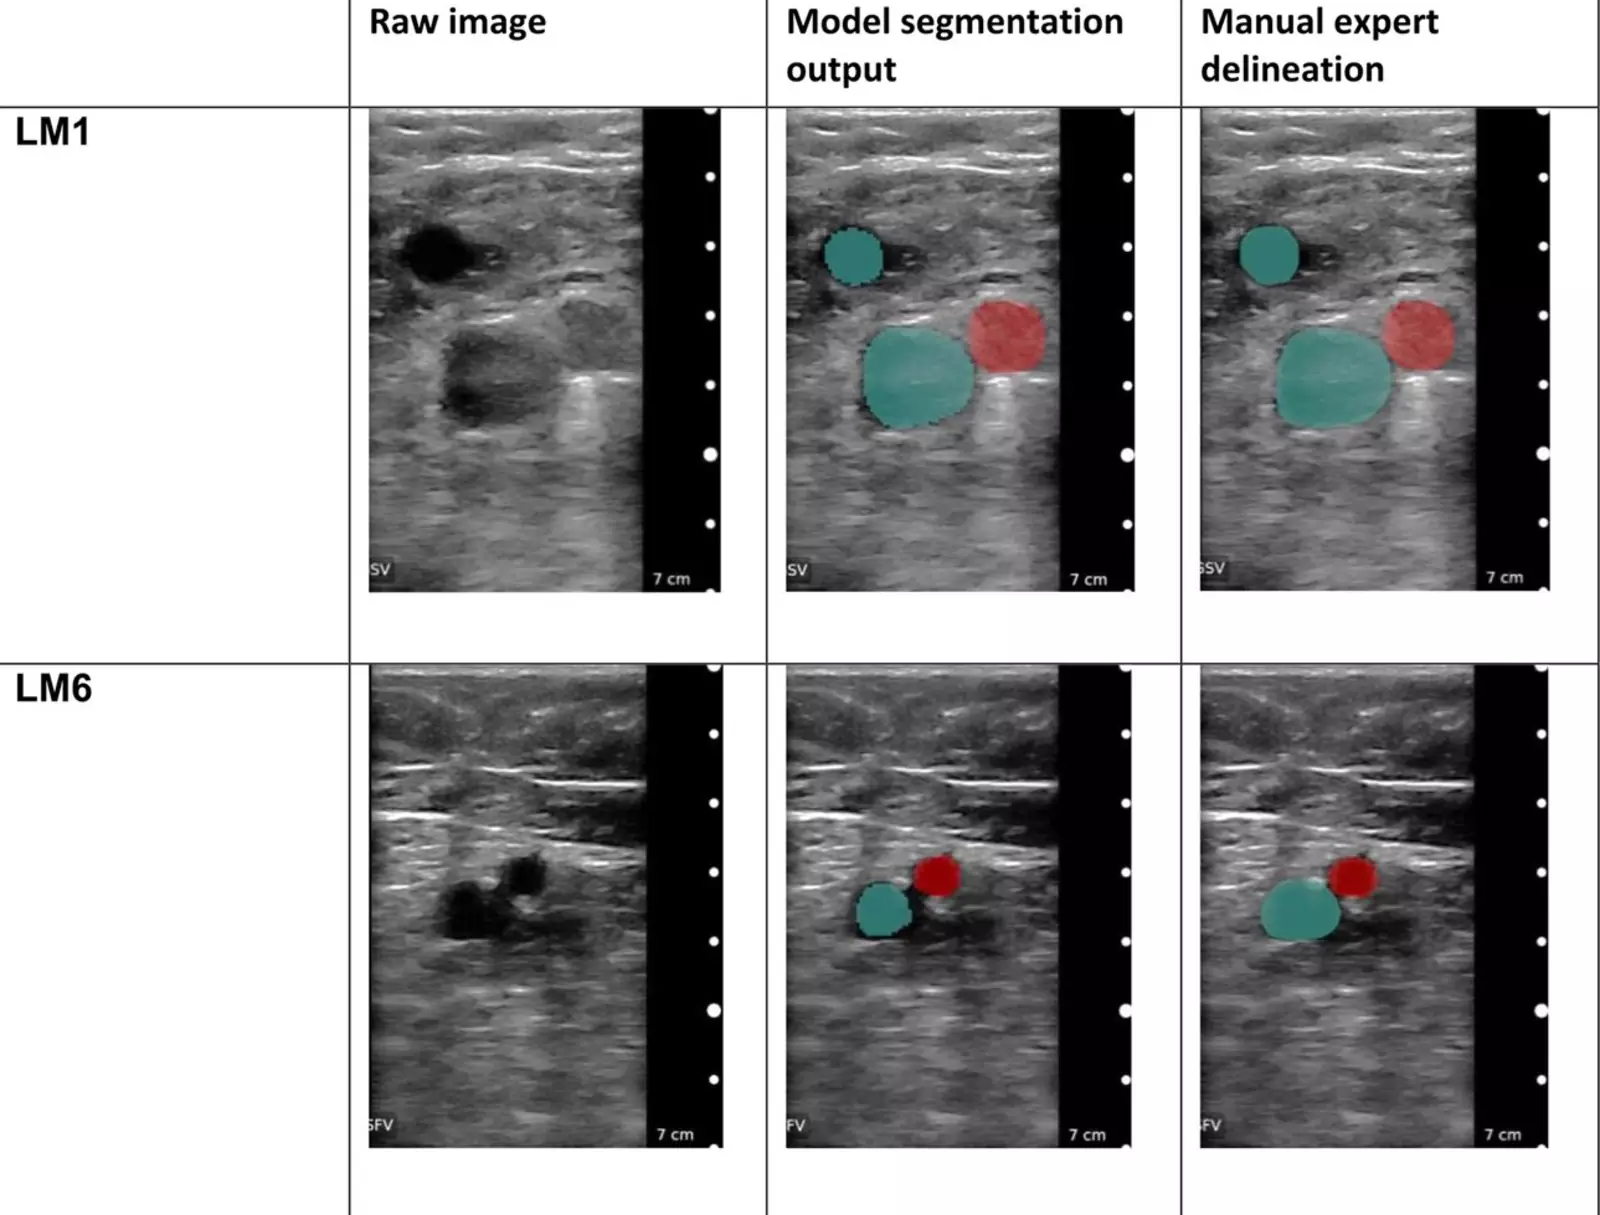

Для анализа машине было предложено отличить снимки больных ног от здоровых. В результате тестирования алгоритм ИИ точно диагностировал заболевание по сравнению с золотым стандартом ультразвукового сканирования.

Открытие ценно ещё и тем, что алгоритм может направлять пользователя с помощью ультразвуковой палочки в нужные места вдоль бедренной вены. Это означает, что любой человек без медицинского образования сможет получить изображения для постановки диагноза.